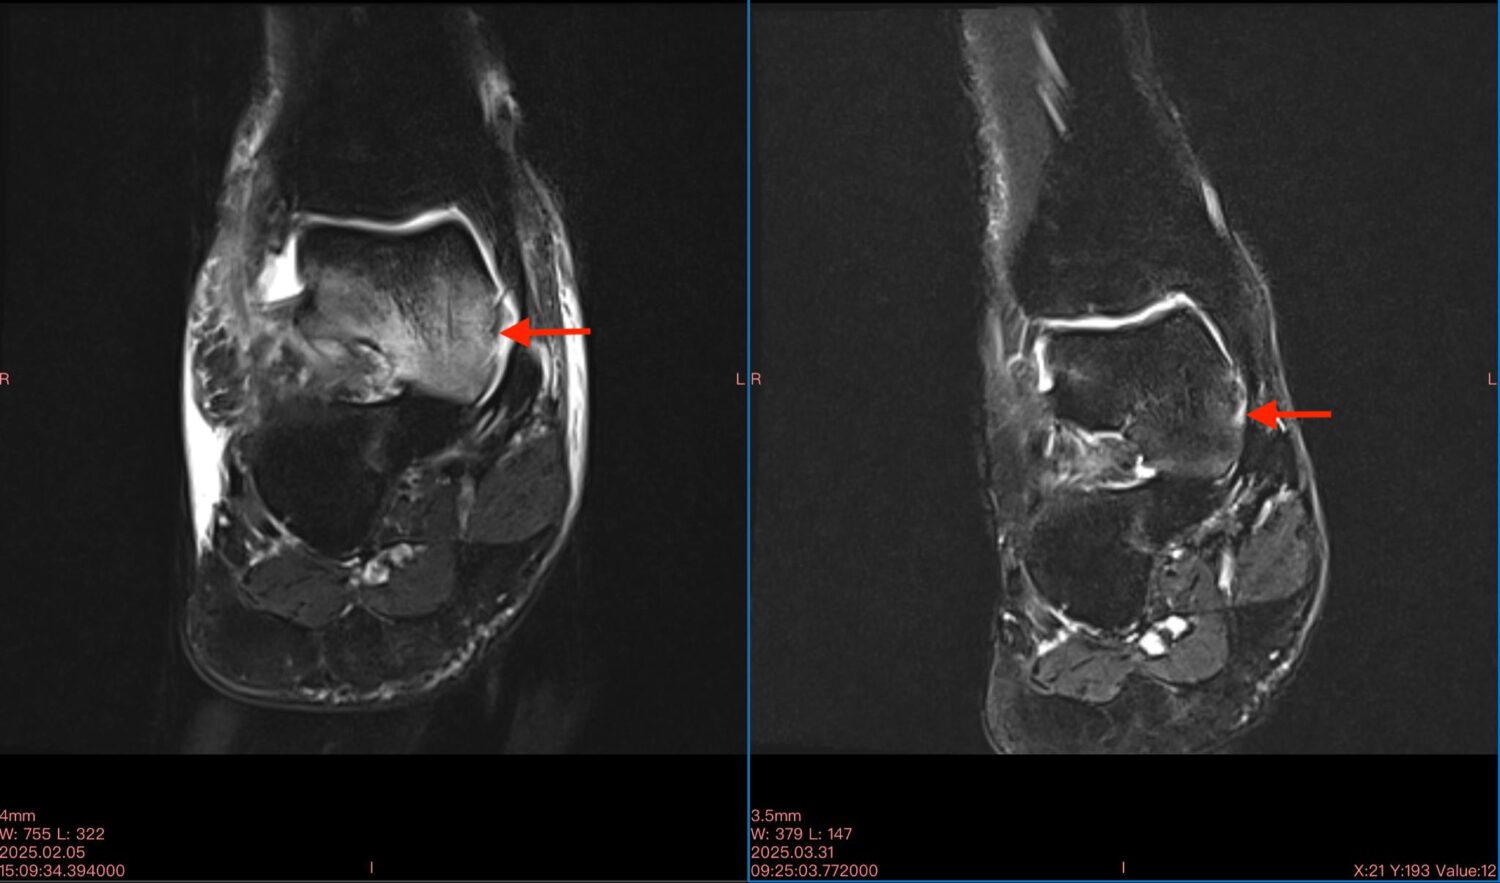

Μαγνητικές ασθενών με οστικό οίδημα πριν (αριστερή φωτογραφία) και μετά (δεξιά φωτογραφία) την θεραπεία με διαμαγνητική αντλία: